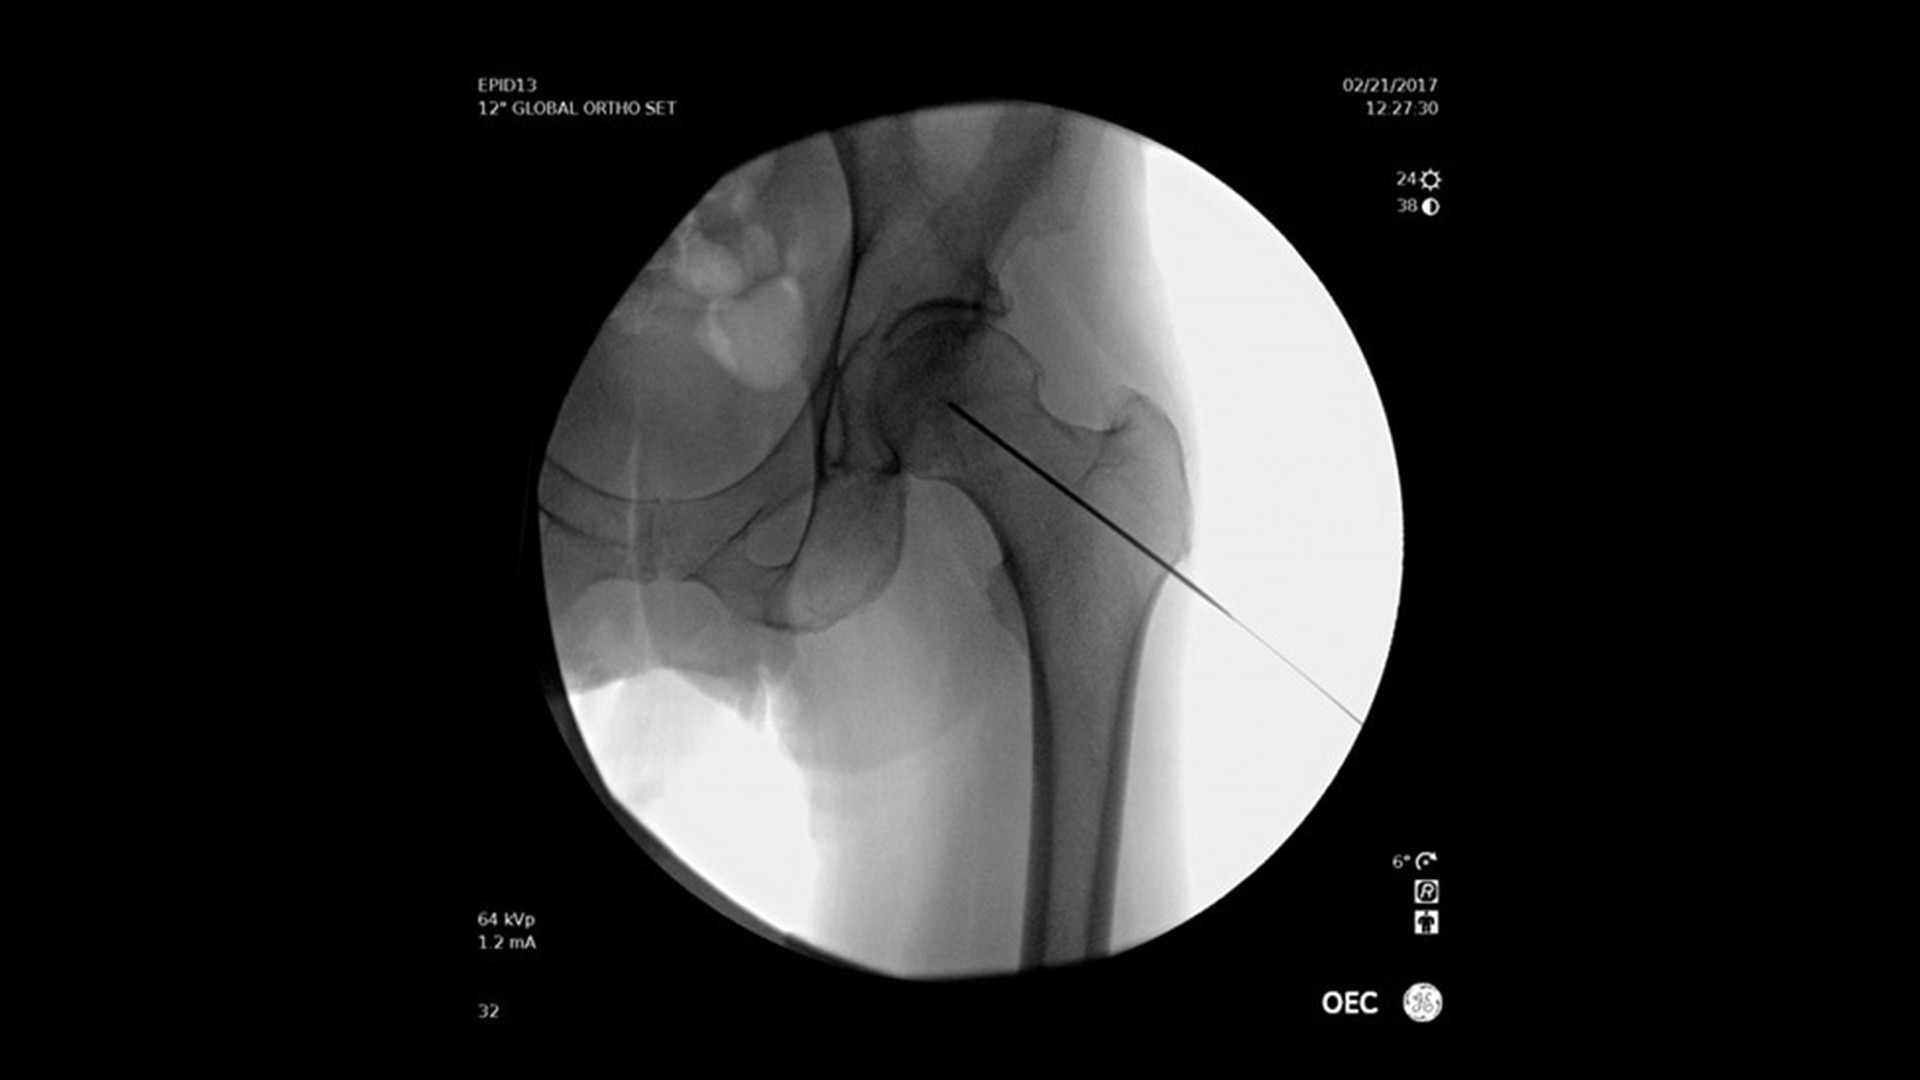

Adquisición de imágenes simplemente mejores

Más informaciónEstudios de casos